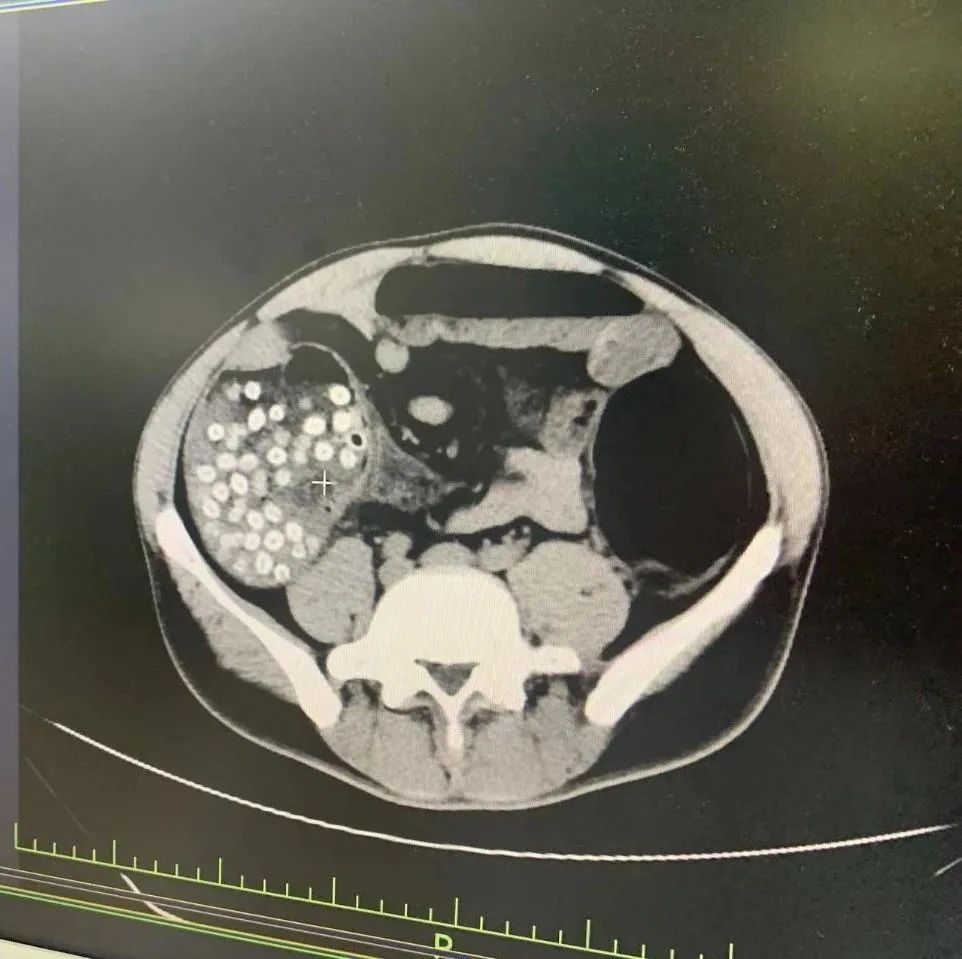

田伯的腹部CT

急诊科主任陆远强主任医师回忆,患者的CT显示有密密麻麻几十个的“小点点”, 这些就是一直没有被排出的杨梅核。